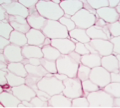

Cells

Tissues

Organs

Systems

Similar cells make up a tissue, and tissues make up organs, and organs that have similar functions make up systems, or organ systems.